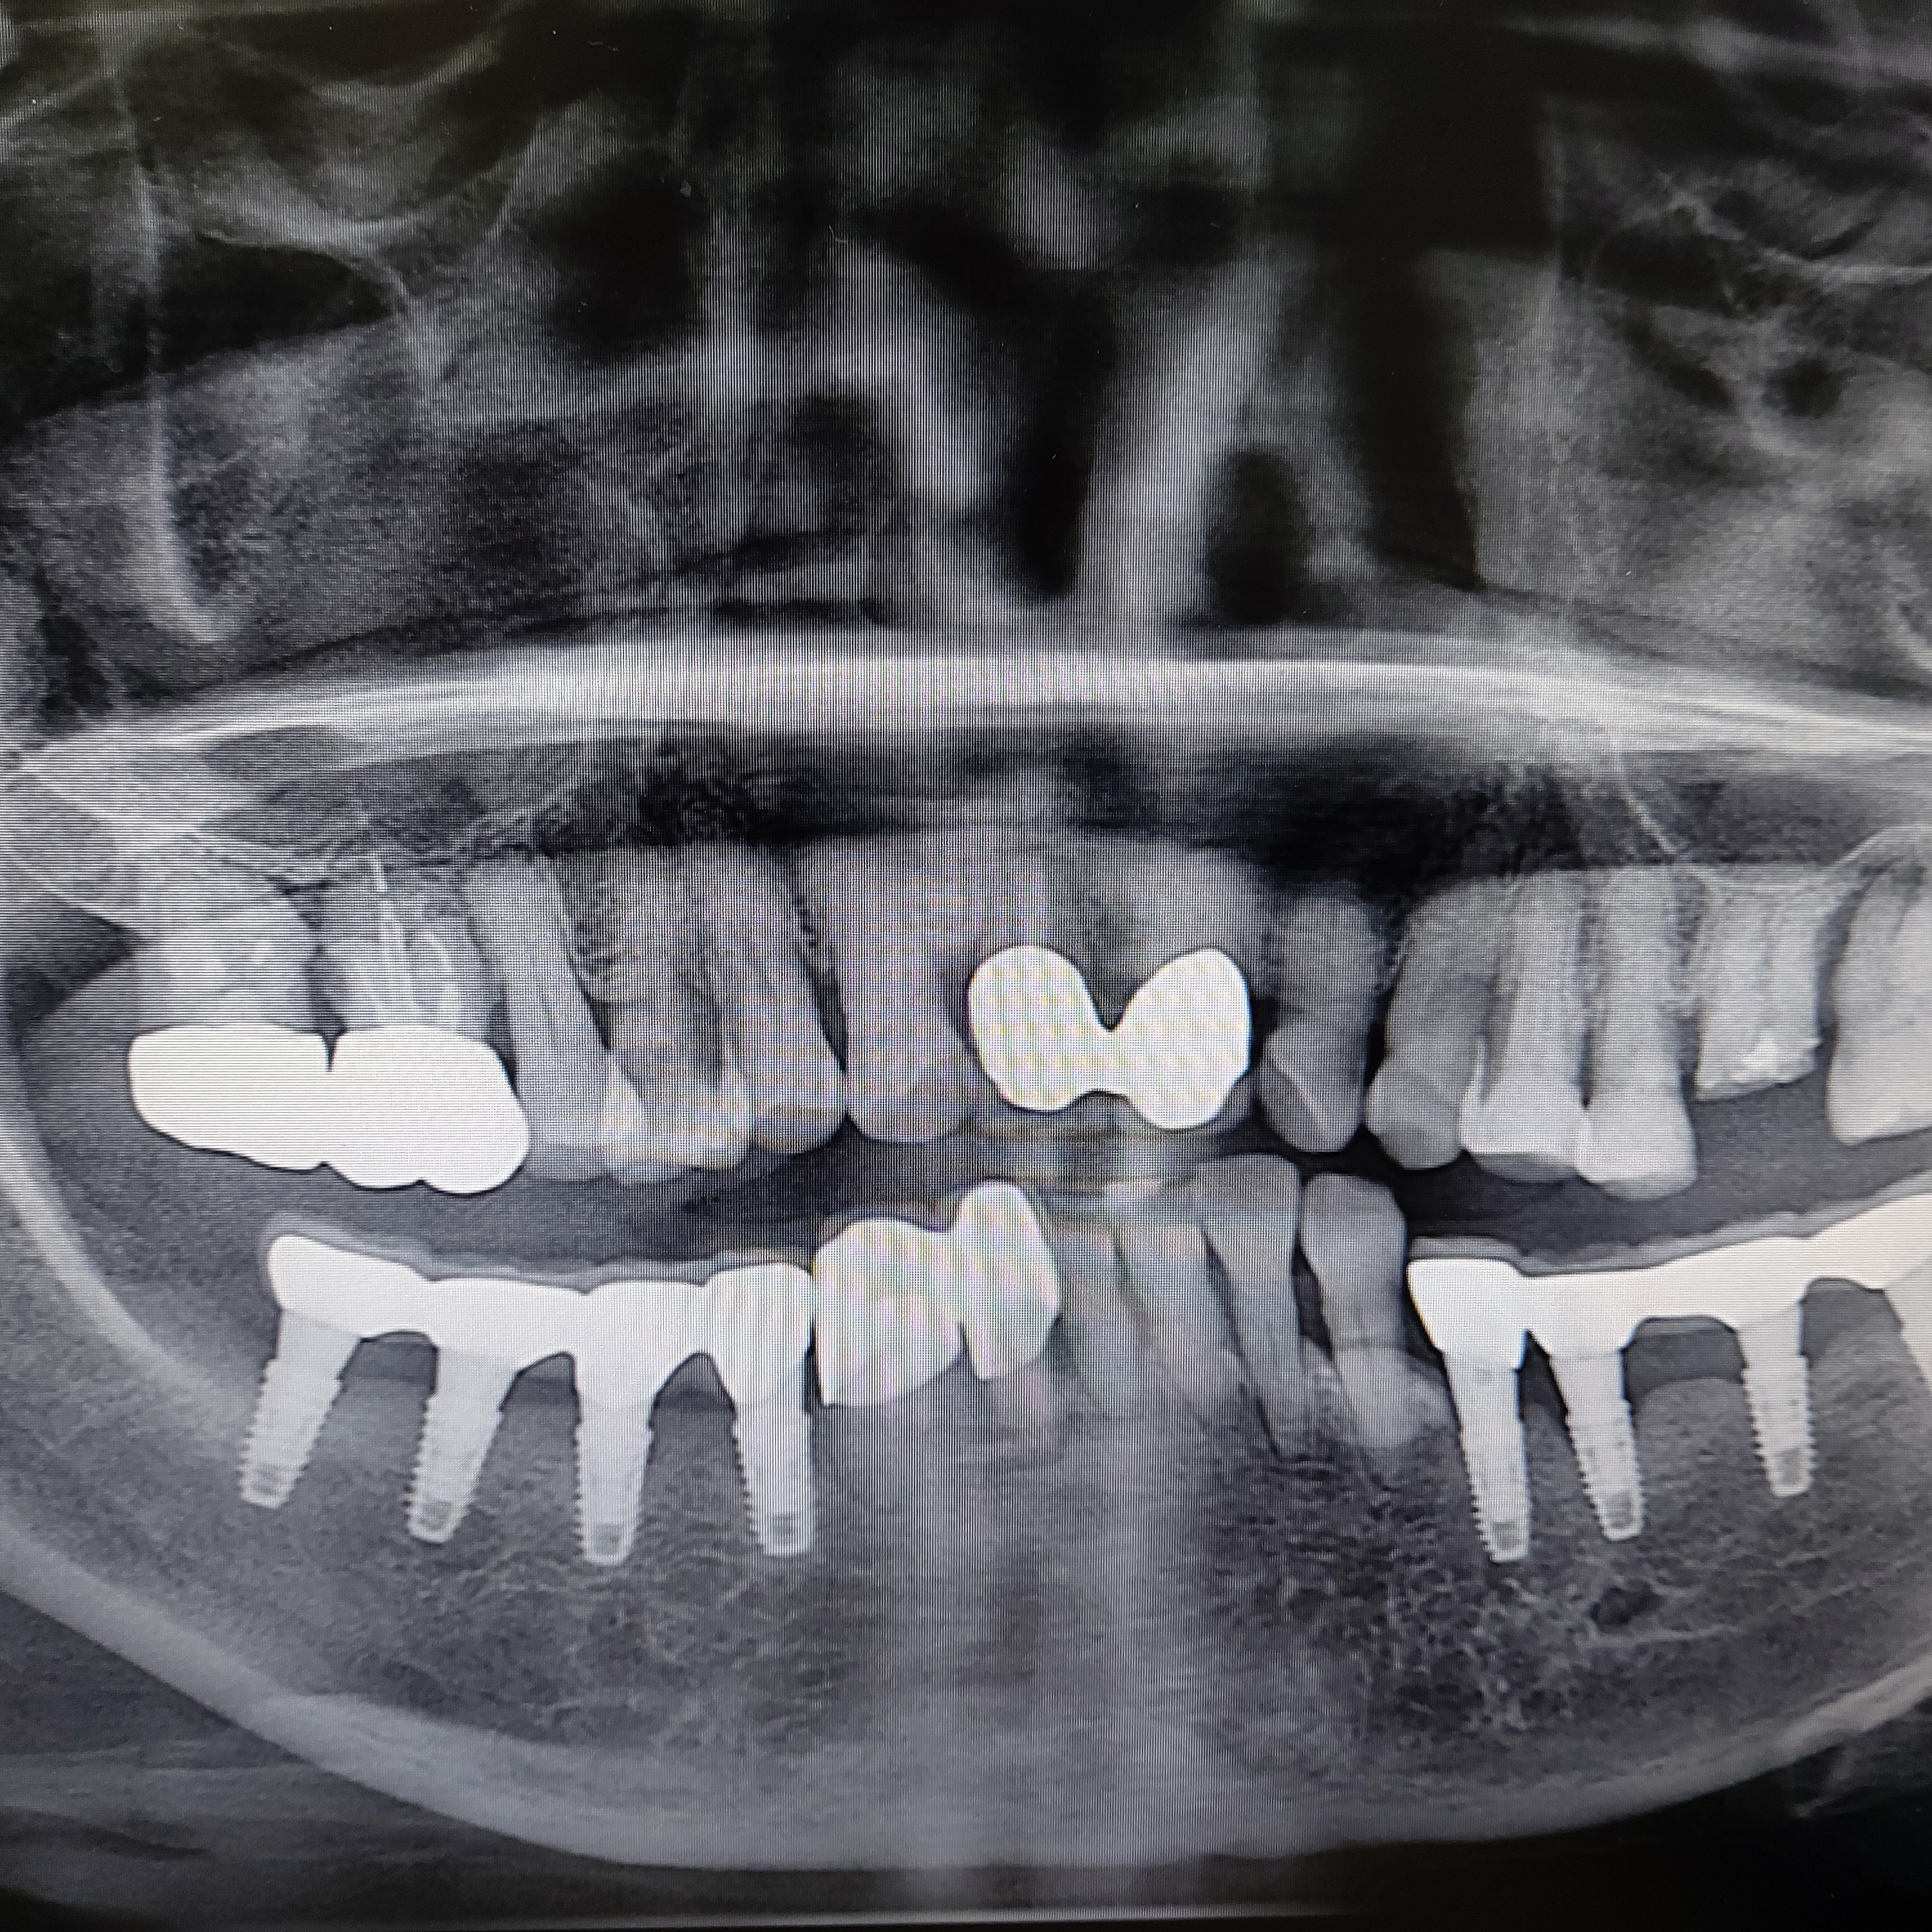

이번 환자분은 하악 전치부 치아가 치주염으로 크라우딩이 심했습니다.

치주가 약하다보니 치아가 힘이 없었고 한쪽으로 기울어져 심미적으로 보기 싫은 상황이었습니다. 물론 동요도도 증가해서 발치가 필요한 상황이었습니다.

환한 미소를 되찾아 드리기 위해 쓰러진 하악 전치부 발치 시행하고 임플란트를 식립하고 4일뒤 바로 이를 올려드렸습니다.

제가 발치 후 즉시 식립을 선호하는 이유는 4가지 정도가 됩니다.

우선 발치 후 바로 식립하기 때문에 치료기간이 많이 단축됩니다

십여년 이상 수술을 해본 결과 지연 식립과 유의미하게 성공율이 차이가 나지 않습니다.

세번째가 하악이든 상악이든 발 치후 즉시 전치부 즉시 식립이 심미적으로 더 좋은 결과를 보입니다.

여기에 더해서 발 치후 즉시 식립 후

바로 이를 올려드리는 즉시부하와의 접목이 환자 분들의 만족도가 아주 높습니다.